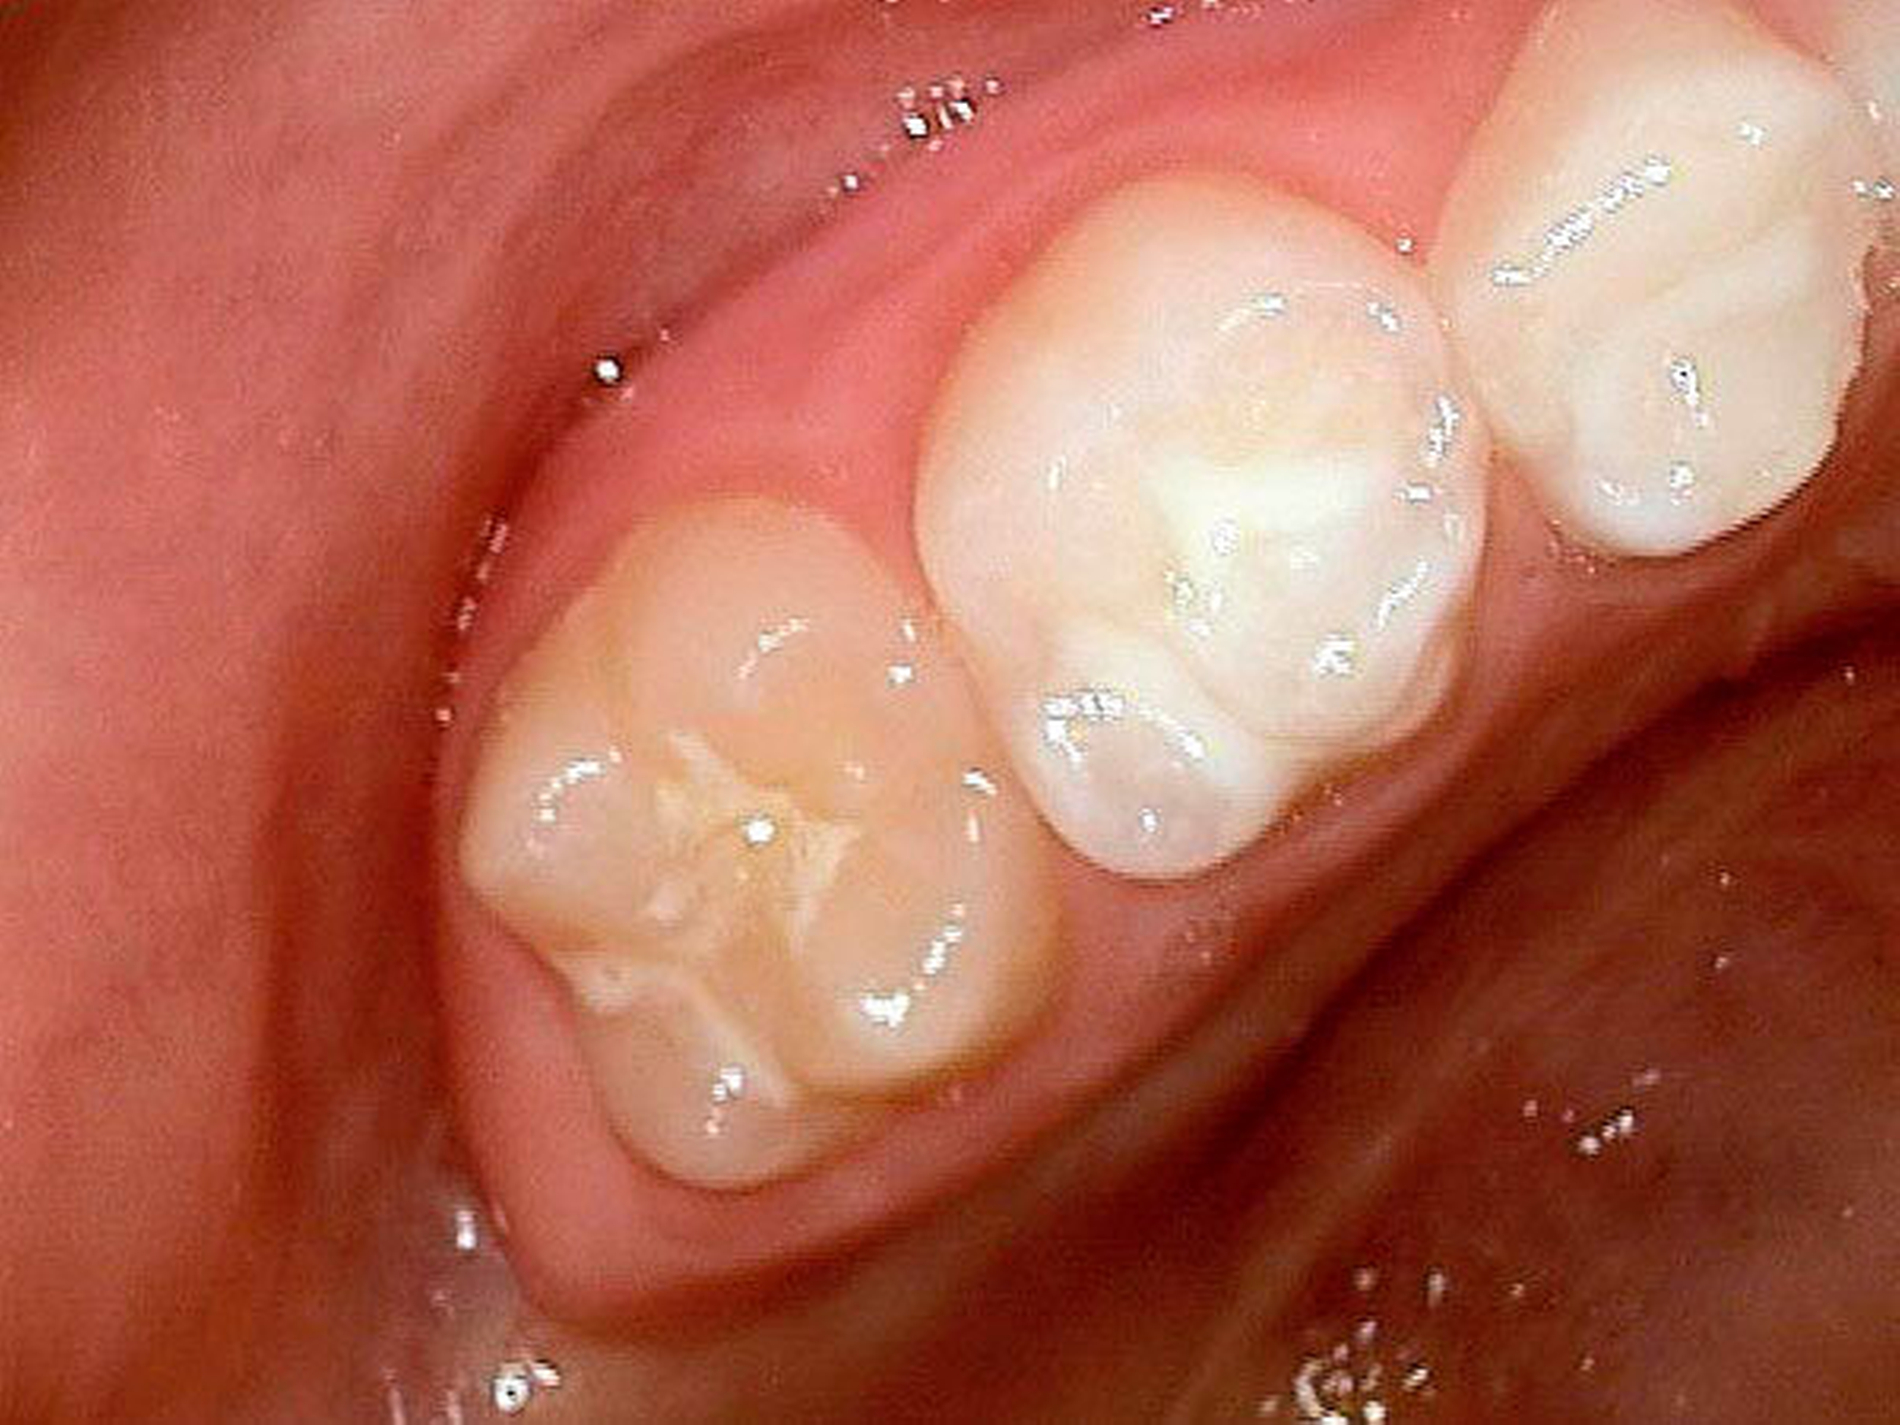

Befund:Abgesehen von einer insgesamt verzögerten körperlichen und dentalen Entwicklung aufgrund der Vorerkrankung, zeigte sich der extraorale Befund unauffällig, der intraorale Befund zeigte ein Wechselgebiss. An allen ersten Milchmolaren konnte Approximalkaries festgestellt werden. Alle Sechsjahrmolaren sowie die Schneidezähne im Ober- und im Unterkiefer waren, unterschiedlich ausgeprägt, von MIH betroffen. Das Zähneputzen und Essen wurde zunehmend zur Belastung aufgrund der Schmerzempfindlichkeit. Außerdem wurde Substanzverlust an Zahn 46 bemerkt (Abbildungen 9 und 10).

Gemeinsam wurde entschieden, dass die nicht so schmerzempfindlichen Frontzähne zunächst so belassen und gegebenenfalls später, wenn die optimale Zahnstellung erreicht ist, mit Füllungen oder Veneers versorgt werden. Die Zähne 16, 26 und 46 sollten mit Keramikkronen versorgt werden (Abbildungen 11 bis 13). Der weniger stark betroffene Zahn 36 sollte, wenn möglich, mit einer Kunststofffüllung versorgt werden. Eine mögliche spätere Extraktionstherapie je nach Engstand oder auch anstelle einer gegebenenfalls notwendigen Weisheitszahnentfernung wurde abgeklärt. Hinzu kam eine Füllungstherapie für die Zähne 64, 74 und 84. Der Zahn 54 wurde extrahiert, da die Wurzelresorption für eine Pulpotomie schon zu fortgeschritten war.